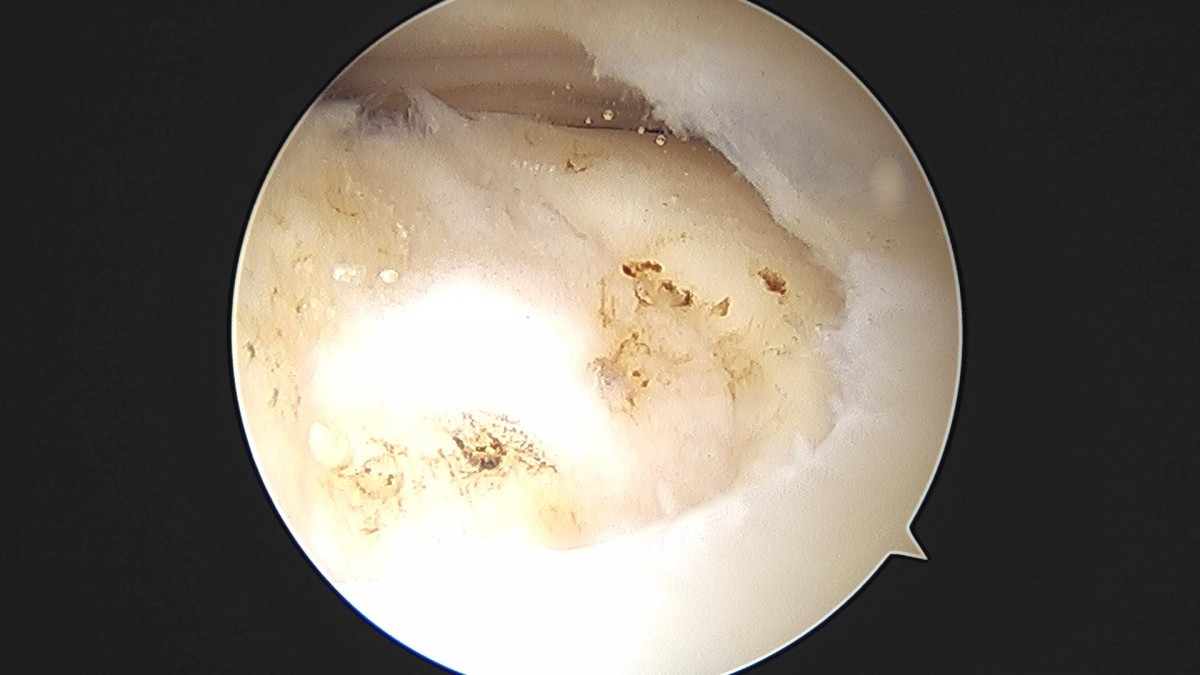

배우한원장님 무릎 반월상연골판 절제술 최갑O 환자

ade708f6ffdfd2e6dcf188e7ecb45ff3_1673514069_2625.jpg